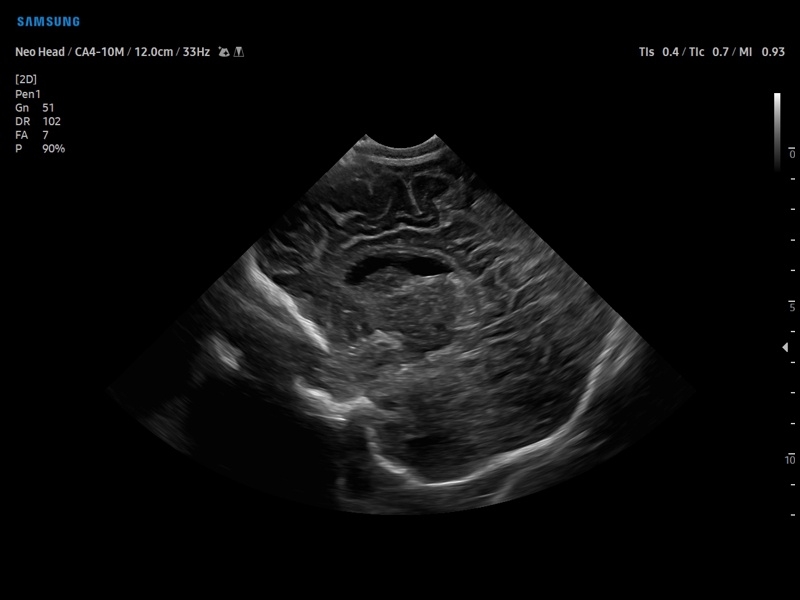

Ультразвуковой сканер V8-RUS является экспертным классом (премиальный уровень) и производится компанией Samsung Medison. Сканер V8 обеспечивает превосходное качество изображения благодаря использованию технологии Crystal Architecture™, которая включает в себя передовое аппаратное обеспечение, монокристальную технологию изготовления датчиков и сложную программную обработку ультразвуковых лучей.

Samsung Medison V8 представляет собой современную ультразвуковую систему, в которой воплощен многолетний опыт компании Samsung в создании эргономичного и интеллектуального диагностического оборудования. Система оснащена передовыми инструментами автоматизации, которые значительно упрощают рабочий процесс и повышают эффективность исследований.

Система Samsung Medison V8 обеспечивает высококачественную диагностику в различных областях медицины:

• Абдоминальные исследования

• Акушерство и гинекология

• Педиатрия и неонатология

• Диагностика костно-мышечной системы

• Транскраниальные исследования